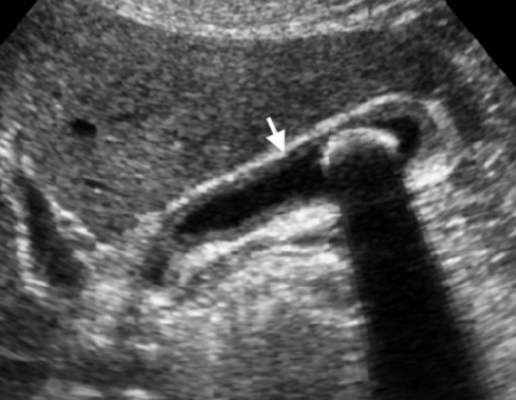

Острый калькулезный холецистит. После контрастного усиления визуализируется растянутый желчный пузырь (белые наконечники) со слегка утолщенной стенкой. Визуализируется камень в шейки желчного пузыря (белая стрелка).

Сверху изображения пациента 62 лет с калькулезным холециститом. На УЗИ визуализируется стенки желчного пузыря растянутые, с субсерозным отеком (указано белыми стрелками) и в просвете желчного пузыря камень и взвесь. На КТ визуализируется переход воспалительного процесса с желчного пузыря на соседние ткани (перихолецистит).